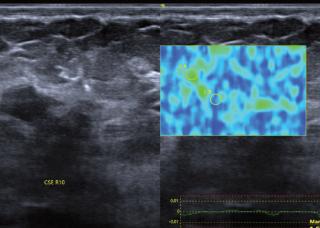

•Elultrasonidomamarioeselestudiode eleccióninicialenmujeresmenoresa35 años,conpatologíamamaria.

•Lamastografíadedetecciónsumadaal ultrasonidoenmujeresconmamadensa aumentalasensibilidaddelaprimeratéc‐nicahastaun87%.

Serecomiendaquelasmujeresdebende continuarconeltamizajeanualmientrasgo‐cendebuenasalud,yrealizarlobajolosestán‐daresdecalidadadecuadosquenosofrecela mastografíadigitalyelultrasonidoespecia‐lizado.Tomarencuentaelcontextoclínico,el riesgoindividualdecadapacienteysobre todonoperderlaperiodicidaddelas evaluacionesporimagenyaquesehademos‐tradoquelasumadelosmétodosdiagnós‐ticoscomolamastografíayultrasonidoau‐mentanlasensibilidaddelabúsqueda.